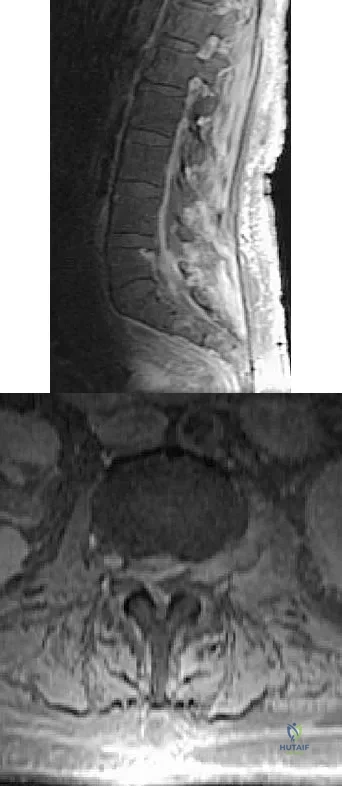

An 81-year-old man with severe low back pain reports right extensor hallucis longus and anterior tibialis weakness and difficulty urinating over the past 24 hours. He has a temperature of 101 degrees F (38.3 degrees C). MRI scans are shown in Figures 31a and 31b. Management should consist of

Explanation